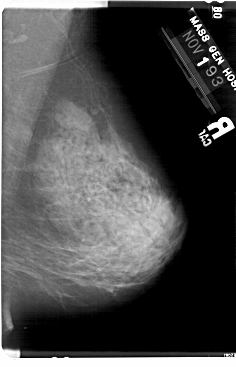

A_1732_1.LEFT_MLO

LEFT_MLO LINES 5491 PIXELS_PER_LINE 3511 BITS_PER_PIXEL 12 RESOLUTION 43.5 OVERLAY